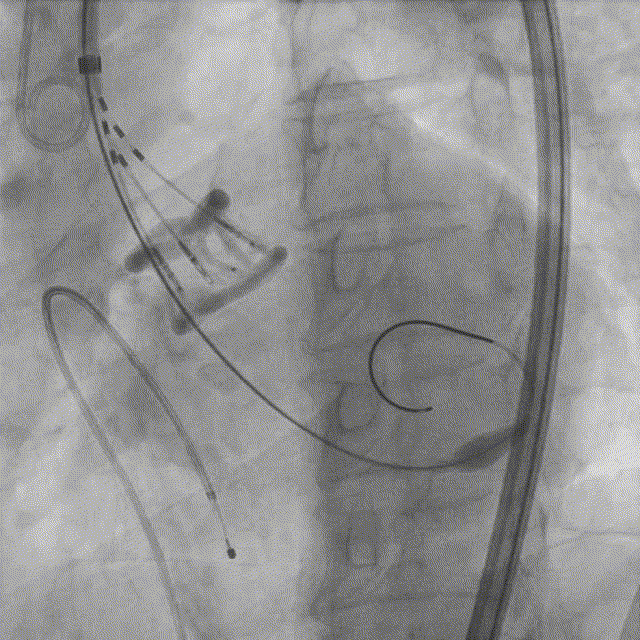

6. 22mm球囊预扩张;

7. Silara A-25mm瓣膜过弓和跨瓣;

8. Silara A-25mm瓣膜左心室初步释放,瓣膜功能良好(不需要左心室快速起搏);

9. Silara A–25mm瓣膜提拉至瓣环水平,反复调整瓣膜位置,形态欠佳,遂用22mm球囊扩张同时充填主动脉环,造影剂显示瓣膜形态及功能良好,完成固化;